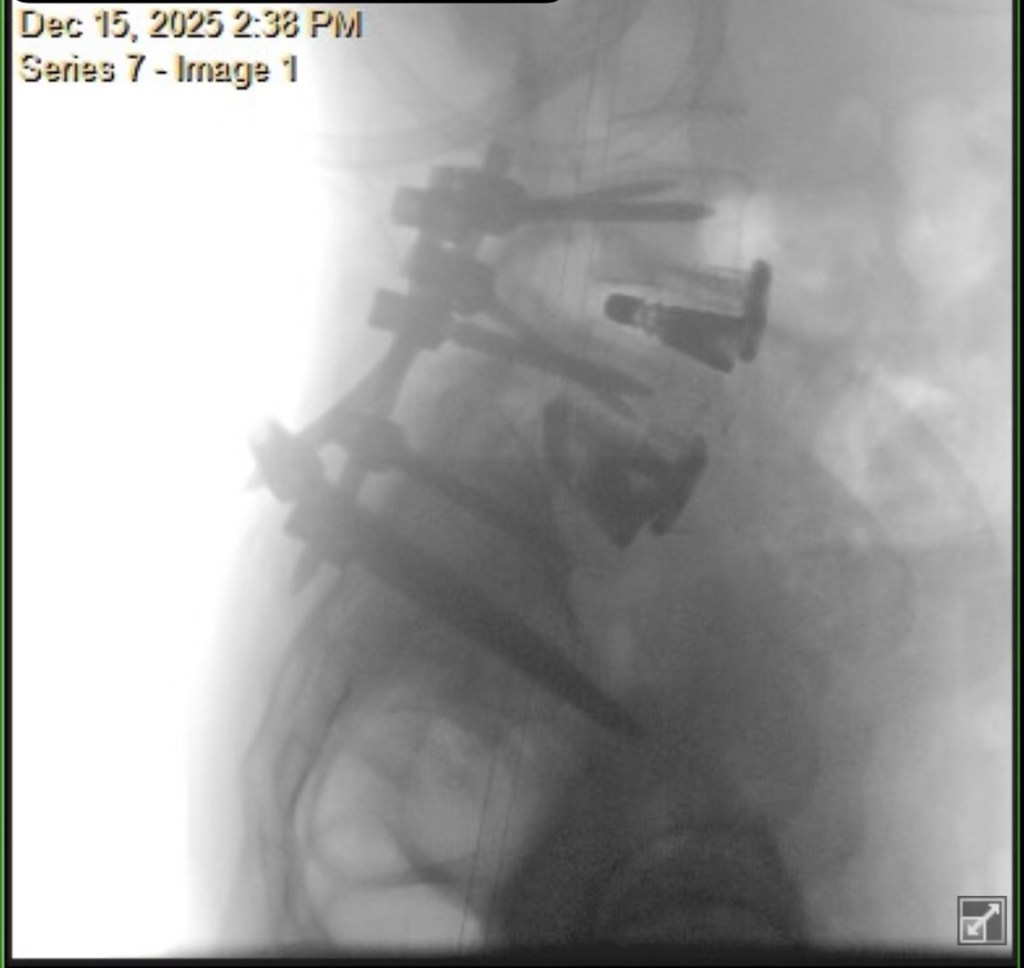

At my 3-month post-op appointment, my surgeon lifted all my restrictions and said I can return to all activity, “just listen to [my] body.” She measured my X-rays (above) and said my lumbar curve decreased 20 degrees, and the thoracic is the same. Also, I grew half an inch. I showed her the scoliosis program I found in New Hampshire, and she was all for it. I’ve booked a furnished apartment in New Hampshire 4/20-5/31 and scheduled the 12 sessions of treatment at the PT clinic there. I’m hopeful that will help with my back pain, and maybe even reduce my thoracic curve. And right before that, I’ll be attending Bionicon!